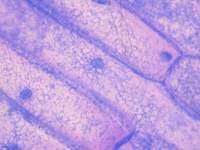

细胞鉴定:神经干细胞采用nestin免疫荧光染色鉴定。左图是白光视野中的“神经球”形态,放大倍数为200x,右图为nestin染色后的荧光图片(绿色),放大倍数为200x。